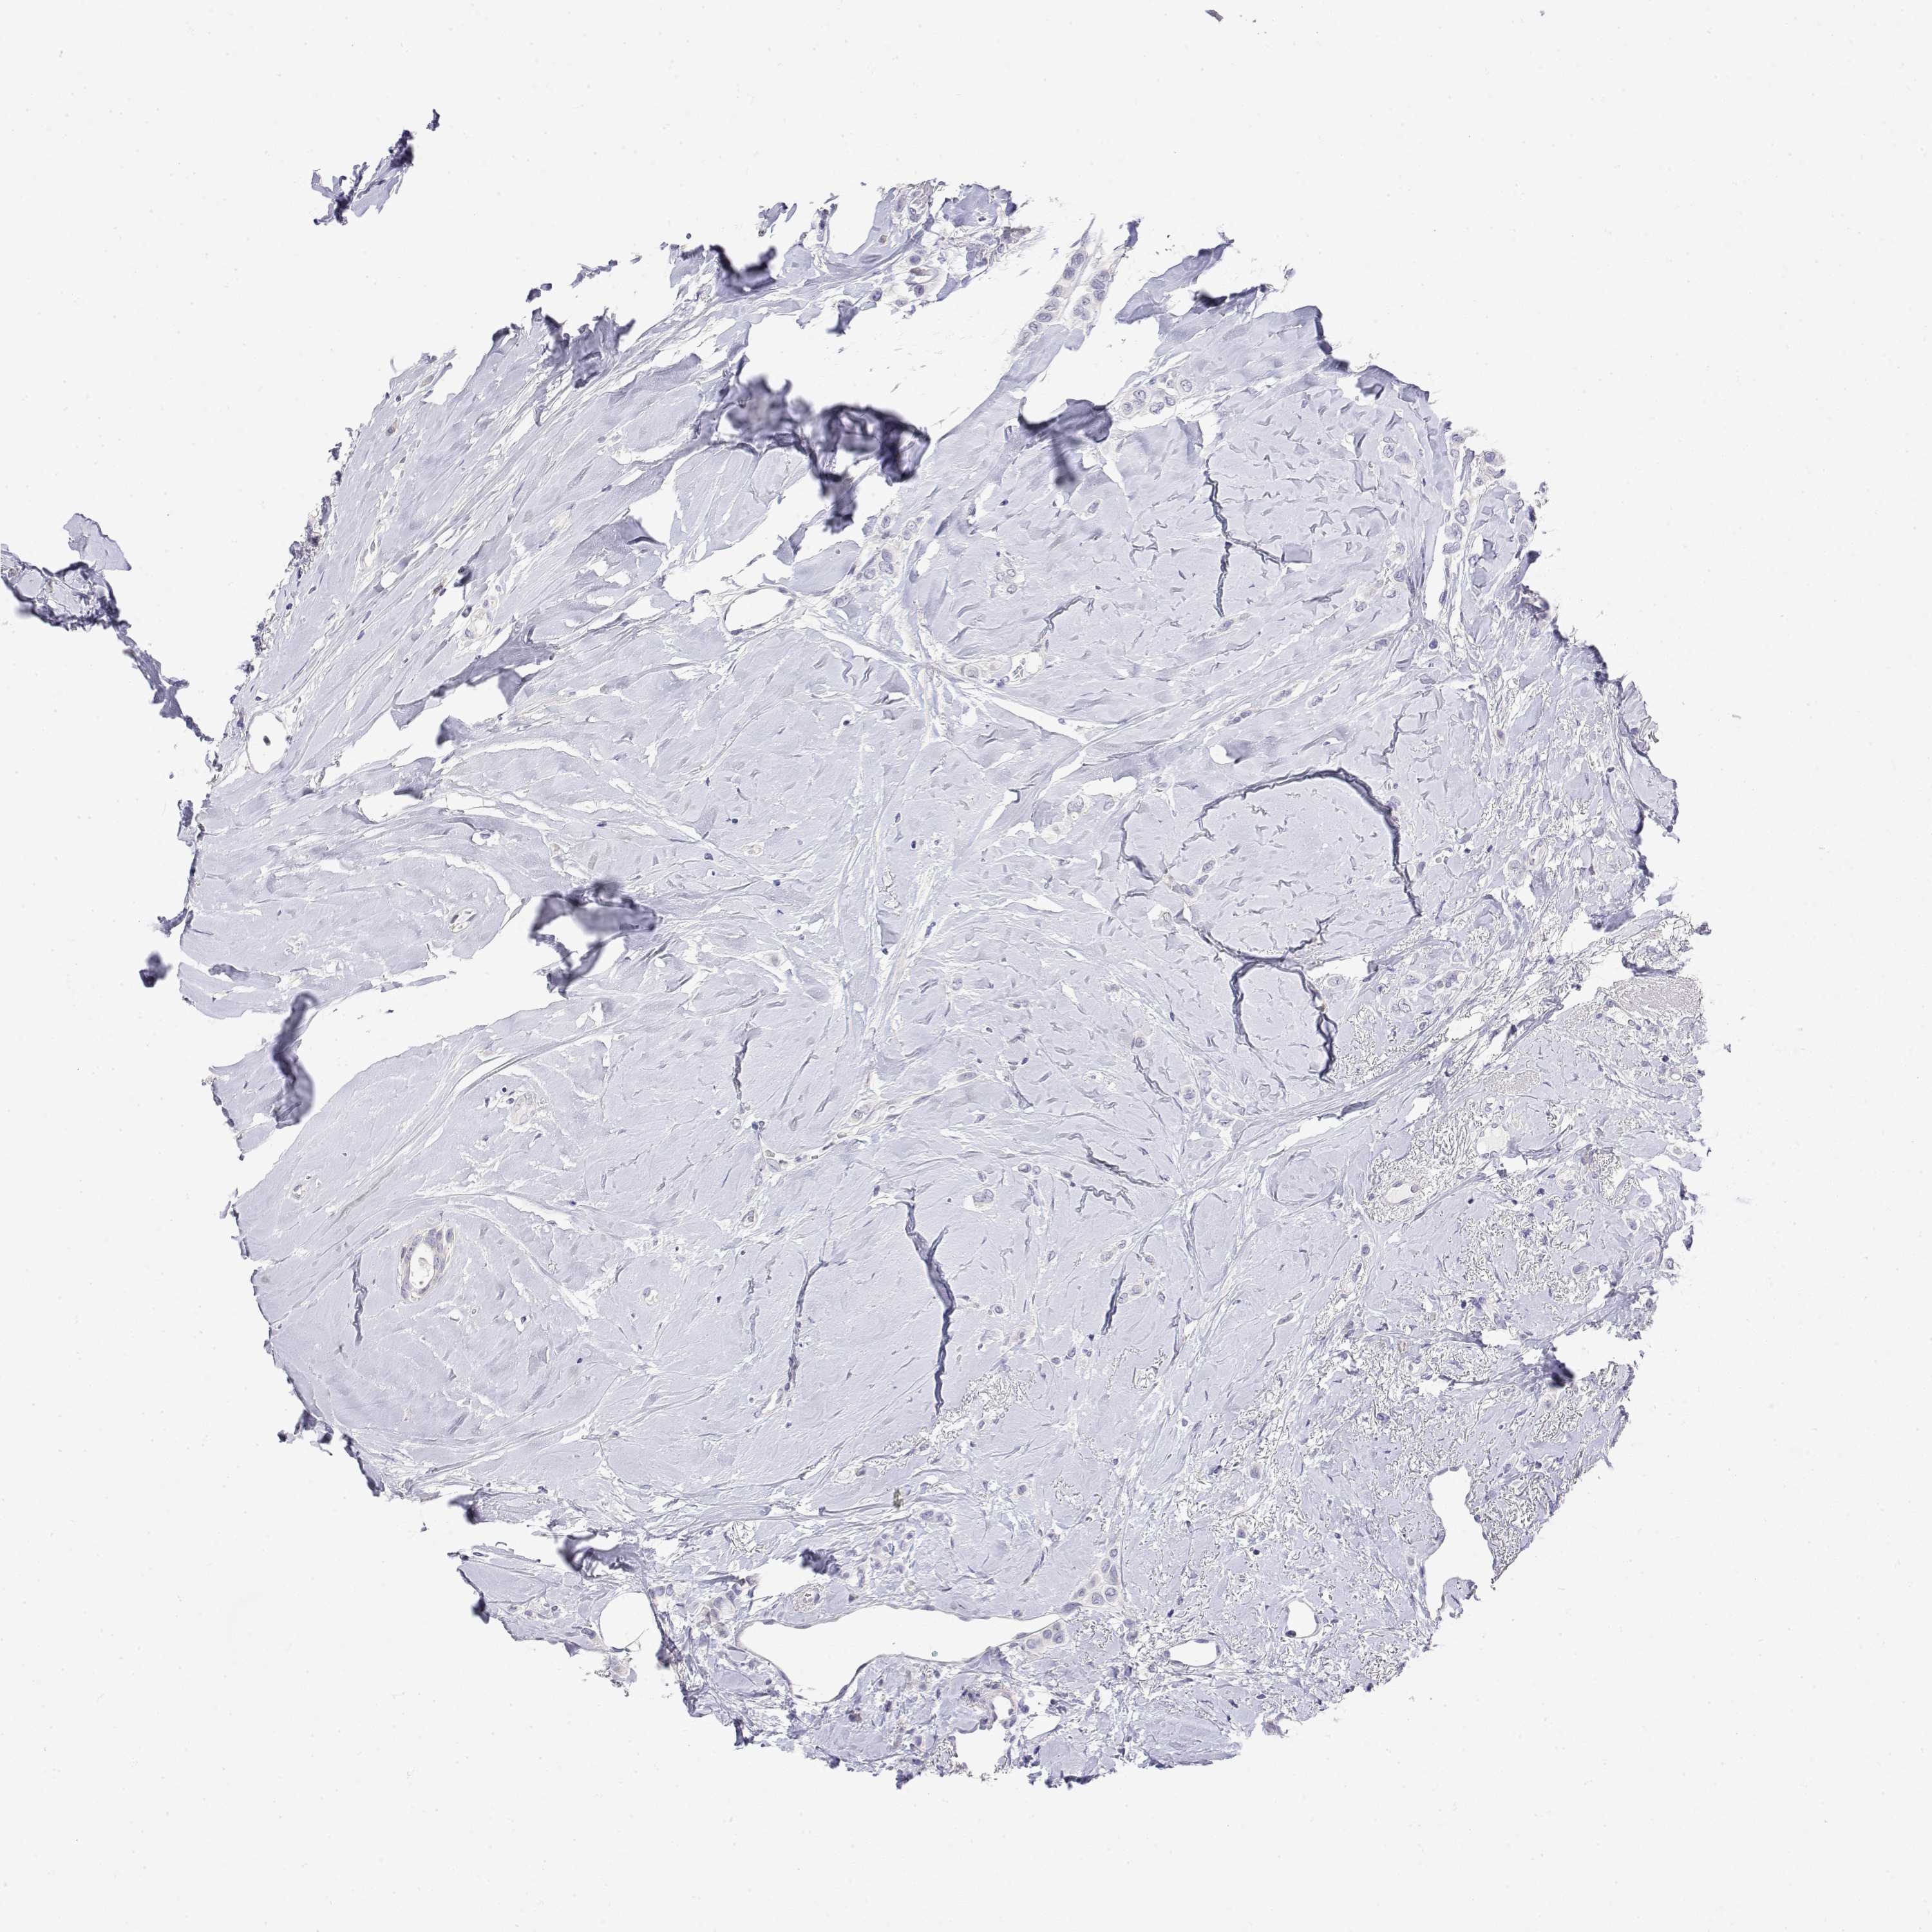

BRCA TCGA BRCA VALIDATION PROTEIN EXPRESSION

Breast cancer

Human cancer